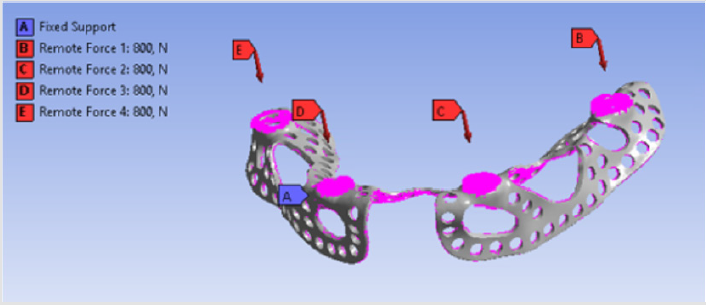

Forces had four points of application on the implant, because dentures were connected to those sites. There were 4 parts between the implant and the denture. 3D models of these connecting components and their assembled state is visible in Figure 5 Component no. 1 was a threaded sleeve that was connected to the baseplate with a welded joint. Component no. 2 was the abutment that had a dual threaded connection with a conical part, which contained a hexagonal fitting geometry for assembly. The height of its lateral wall compensated the necessary gum tissue thickness. This surface was the most crucial part of the system, because it provided epithelial tissue adhesion and bacterial isolation between the oral cavity and tissues. Component no. 3 was the bonded interface containing the base for screw fixation to which the crown was fixed. Part no. 4 was a fixing screw with hexagonal connection. Figure 6 shows our tested implant with occlusal forces and fixation support areas. A sleeve was welded into the implant and the abutment was inserted inside. Fix constraints were chosen because the implant could not move on the bone tissue.

Distant forces were used as they would normally act on the implant from the dental crown. We used data obtained from scientific literature according to which magnitude occlusal forces can be between 100 and 800 N. In the first analysis, maximum 800 N occlusal force was defined. Its result is presented in Figure 7 It is notable that stresses only raised at the acting point of the force. Stress intensity was 287.28 MPa for maximum occlusal load. Another scenario was also investigated in which the frontal part of the implant was loaded with the lowest, while the back of the implant was loaded with the highest occlusal forces. Figure 8 presents the results of this loading scenario with the maximum stress level of 207.6 MPa. It is notable in this case that highest stresses raised at the back of the implant at the acting points of the forces. Different force variations were all analysed from minimum to maximum loads. Figure 9 shows the set of completely linear results. Highest stress intensity was 287.28 MPa for maximum occlusal forces. The studied implant was inserted after manufacturing. Implant fitting to the bone ridge of the patient can be seen in Figure 10.